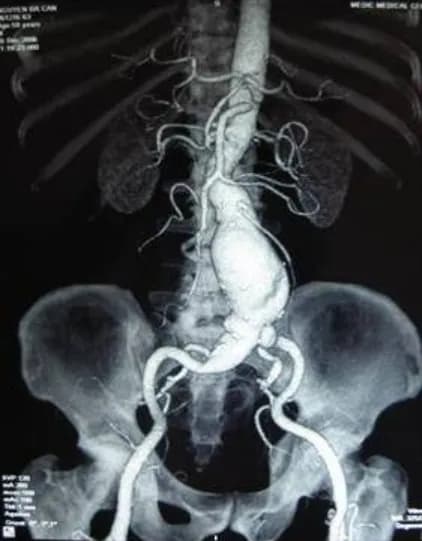

Các trường hợp chống chỉ định can thiệp mạch vành

Bài viết trình bày về can thiệp mạch vành qua da (PCI), một thủ thuật điều trị bệnh động mạch vành. Nội dung bao gồm các...